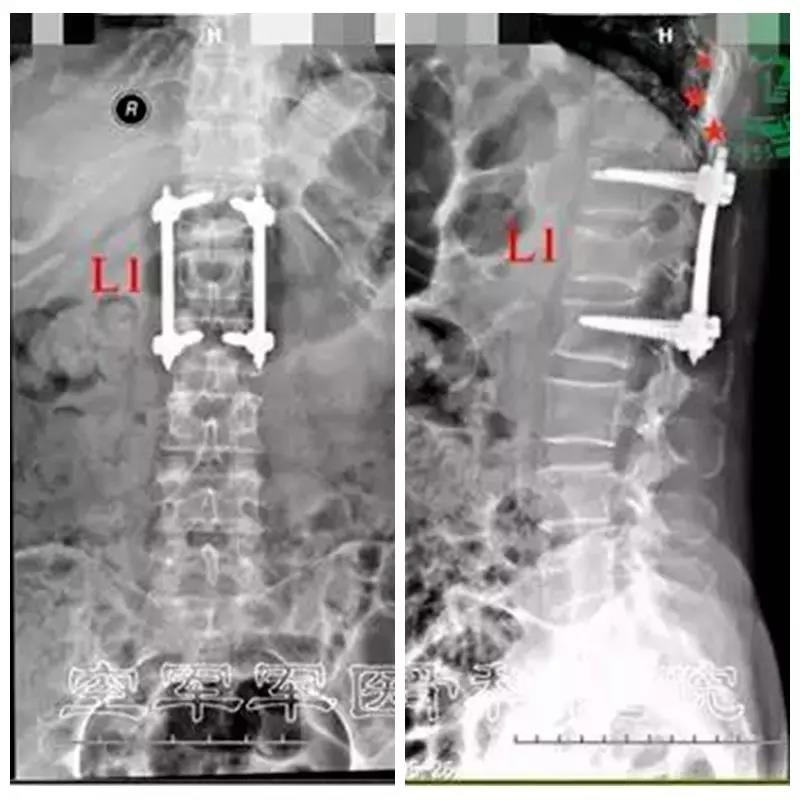

微创导航下单平面螺钉系统腰椎骨折复位内固定术

患者:张某,女,56岁

主诉:高处坠落,腰背部疼痛7小时。

既往史:平车推入病房,强迫体位。腰1椎体棘突压痛+,叩击痛+,双下肢及肛周、会阴区皮肤感觉正常。双下肢肌力正常。双侧膝腱反射、跟腱反射正常。病理反射未引出。

诊断:腰1椎体压缩性骨折

术前X线正侧位片

术后X线片正侧位及三维CT